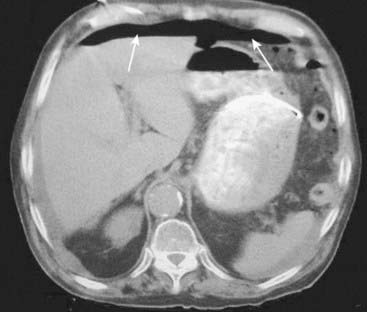

image

Figure 15-15 Portal venous gas.

A, Numerous small black branching structures are visible over the periphery of the liver (white circle). This is air in the portal venous system, a finding most often associated with necrotizing enterocolitis in infants but which can also be seen in adults, usually with bowel necrosis. Unlike air in the biliary system, this air is peripheral rather than central and has numerous branching structures rather than the few tubular structures seen with pneumobilia. B, Close-up of axial CT scan through the liver shows air in the portal venous system (solid white arrows) in a patient with mesenteric vascular disease.